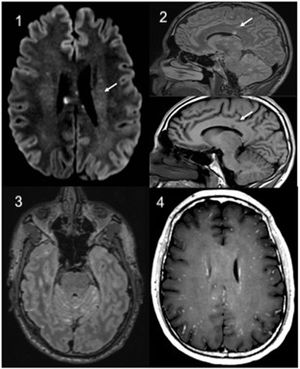

Estudios complementarios: hemograma, bioquímica general, proteína C reactiva y coagulación, normales. La punción lumbar objetivó hiperproteinorraquia, con Gram, PCR panbacteriana y de micobacterias negativas. Las serologías de lúes, VIH y virus neurotropos, así como ANA, ANCA y HLA-B5 fueron negativos. Un vídeo-EEG mostró datos de encefalopatía difusa leve y la TC craneal fue normal. En la RM craneal se objetivó la presencia de múltiples lesiones puntiformes supra e infratentoriales en leptomenínges y en cuerpo calloso en «snow-ball» (fig. 1).

RM cerebral: 1: Axial. Difusión con lesiones puntiformes hiperintensas en relación con microinfartos. 2: Sagital, Flair T2 y sagital T1. Afectación característica del cuerpo calloso. 3: Axial Flair T2 con cte. Hiperseñal y realce leptomeníngeo (señal aditiva T1 cte + T2). 4: Axial T1 cte con patrón de capación «miliar».

Se diagnosticó de un síndrome de Susac (SS) ante la tríada clínica de encefalopatía, hipoacusia neurosensorial y vasculitis retiniana con oclusiones arteriales. El SS es una endoteliopatía microvascular oclusiva inmunomediada y pauciinflamatoria que afecta al cerebro, a la retina y al oído interno, descrita por primera vez en 19791,2. Son características las lesiones en la RM en T2 FLAIR en «bola de nieve» a nivel del cuerpo calloso y la vasculitis retiniana oclusiva en la AFG3.